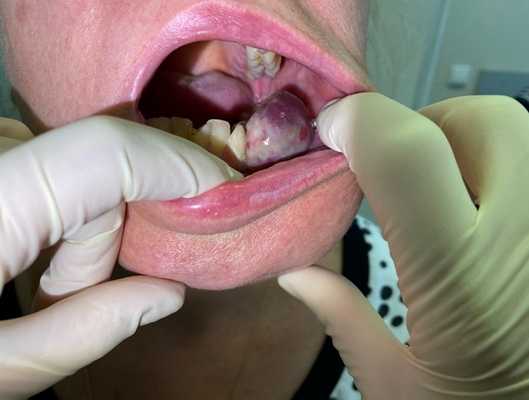

— Осмотр опытного специалиста, врача-онколога; На фото можно увидеть, как выглядит саркома мягких тканей:

— Рентгенологическое исследование. Позволяет визуализировать тень опухоли, деформацию прилежащих к опухоли фасциальных перемычек, выявить изменения в костях;

— УЗИ опухолей мягких тканей. Это метод диагностики как первичного очага, так и поражения региональных зон. Позволяет определить границы опухоли, связь с окружающими органами, структуру опухоли;

Рисунок №1. Саркома мягких тканей бедра. УЗ-картина в серошкальном и сосудистом режимах визуализации